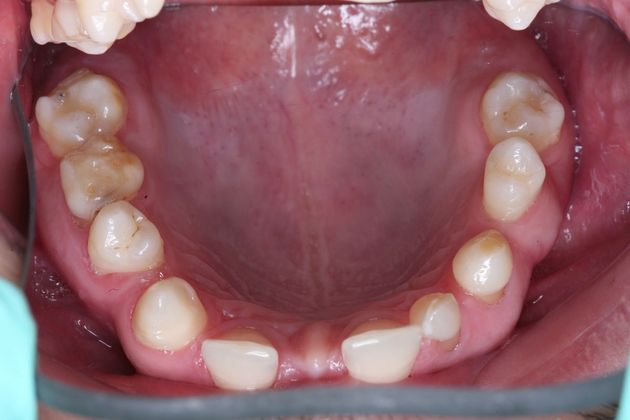

Full mouth rehabilitation. This 20 year old patient had emigrated from Bosnia only a few years earlier with his mother and two sisters after his father had perished in the Bosnian/Serbian conflict. He had severe hereditary dental dysplasia, with multiple retained baby teeth where permanent teeth never formed. He had a total of nine missing teeth, and the teeth that were present were not in their correct positions, leading to a poor bite relationship and multiple large gaps throughout his mouth. He was embarrassed to smile and wanted to know what could be done. His was a very complex case requiring Smile design and; the services of an oral surgeon to take out the baby teeth and strategically place implants at different times of his treatment, an orthodontist to level, straighten and create the proper size spaces for the placement of nine implants, gum sculpting, whitening, and the placement of fillings and crowns on natural teeth, and crowns on the nine implants. It took some time, but he got a great result and the resulting confidence has helped him go to college, get a better job and have a social life! Procedures: Smile design, oral surgery and implant placement, orthodontics, gum lift, whitening, fillings and crowns. TESTIMONIAL:" Dr. Balloch is a very skilled, compassionate and empathetic dentist who develops a personal relationship with his patients. He is (by far) the best dentist that I have experienced in my 85 years. His dental and office staff are equally friendly and professional. Dr.Balloch definitely exceeded my expectations. I highly recommend!"